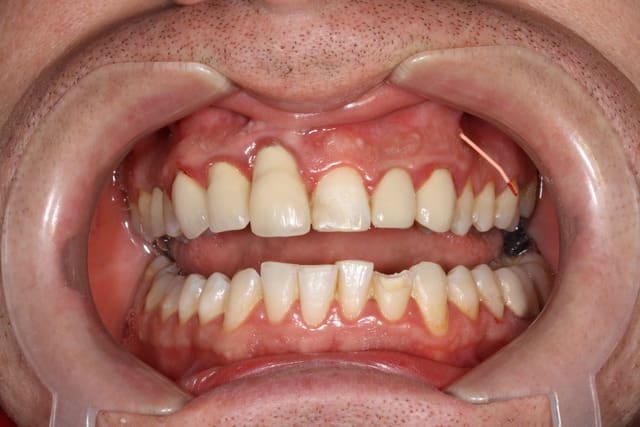

Sur ta photo clinique, je vois que tu as utilisé un cône de gutta : l'obturation a retro transfistulaire est une technique délicate. Vu que tu débutes, essaie plutôt un bon bourre-pâte methasone/salive.

Ceci dit pour être honnête je suis assez surpris par le boulot de leur prothésiste, c'est pas mal d'un point de vue esthétique !

en tout cas tu as beau être en 6eme année, tu es un chef en paro.. félicitation.. contrôle de plaque/tartre impeccable.. pourtant le patient n'était pas très motivé au départ!!!

en en chir paro...ta greffe sur la 11 a bien pris.. on ne voit presque plus le décalage des collets !!

C'est vrai que n'étant adepte de la paro , ou de l'extraction et n'ayant pas de correspondant ou de paro en mutuelle , le praticien s'est excellemment débrouillé et le prothésiste c'est bien appliqué sur la fausse gencive ; sans mal d'ailleurs car les préparations intrasulculaires et sous gingivales ça aide ...